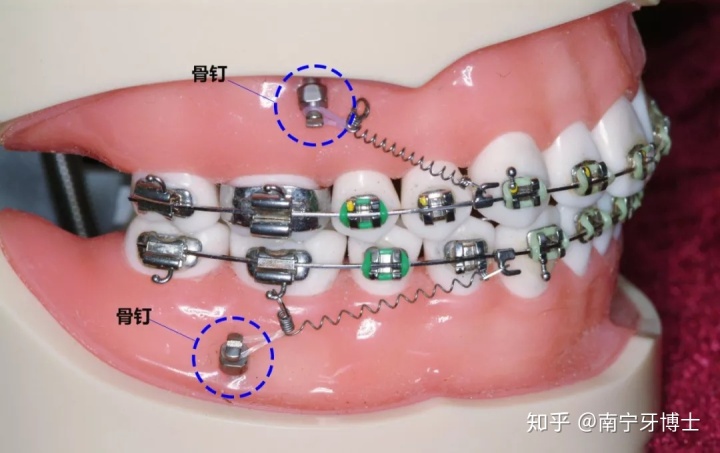

迷你骨钉简称骨钉,又叫支抗钉、种植钉,学名“种植支抗”或“暂时性支抗装置”,由纯钛或不锈钢制作,是植入牙槽骨的临时性迷你小钉子,矫正结束后就会移除的,而骨钉缺口会自行复原长好。

骨钉的功能是提供施力的固定源,帮助拉动牙齿,24小时施力,可以达到传统矫正很难做到的效果,能够快速改正龅牙脸型,真正做到该动的牙动,不该动的牙不动,提高矫正效果和时间。

骨钉是什么样子的?

它长得和普通的钉子很像,但体积很小,一般长度6mm~12mm不等,直径1.5mm左右。不同大小的钉子所用于植入的位置不一样,一般后牙区用长一些的,前牙区用短一点儿的,因为牙槽骨的厚度不一样。